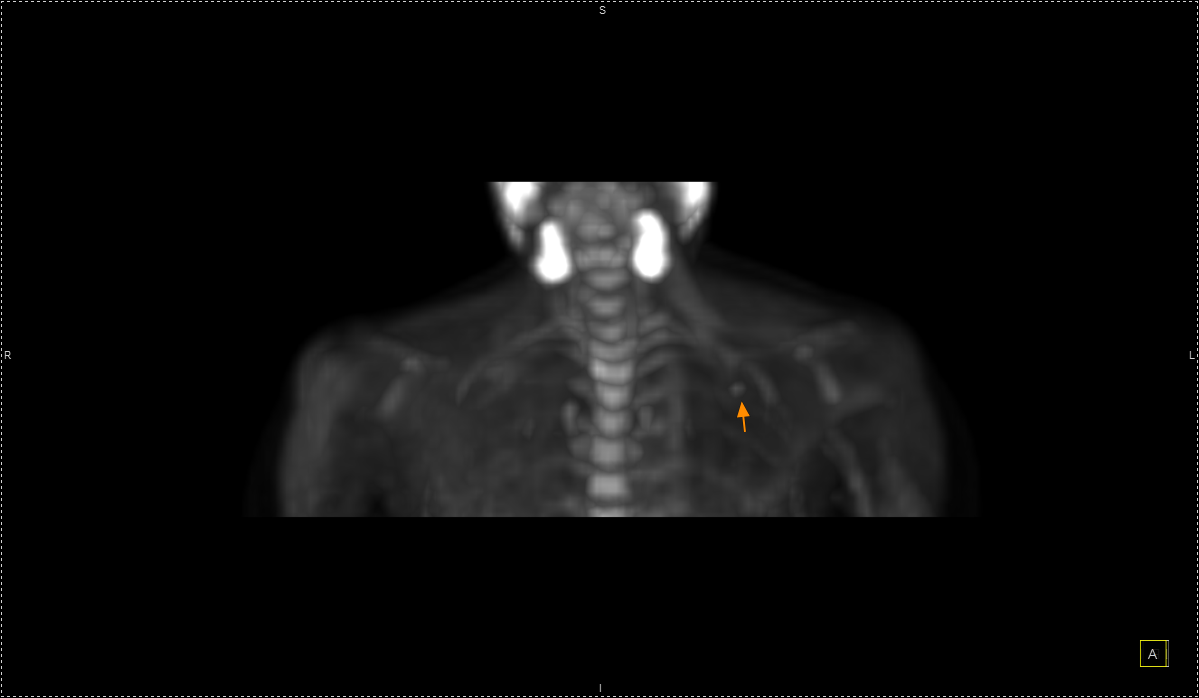

Oncofreeze AI – Διόρθωση των παρασίτων από την αναπνευστική κίνηση κατά τη διάρκεια της εξέτασης μέσω τεχνητής νοημοσύνης.

Με τη χρήση ειδικού λογισμικού Τεχνητής Νοημοσύνης (MIM – Lesion ID) πραγματοποιείται αυτόματος υπολογισμός της έκτασης και του όγκου των θέσεων ενεργού νόσου. Ξεπερνώντας τις δυνατότητες του ανθρώπινου οφθαλμού υπολογίζεται το συνολικό φορτίο νόσου πριν και μετά την θεραπεία επιτρέποντας ακριβέστερο χειρισμό του ασθενούς από τον θεράποντα ιατρό.